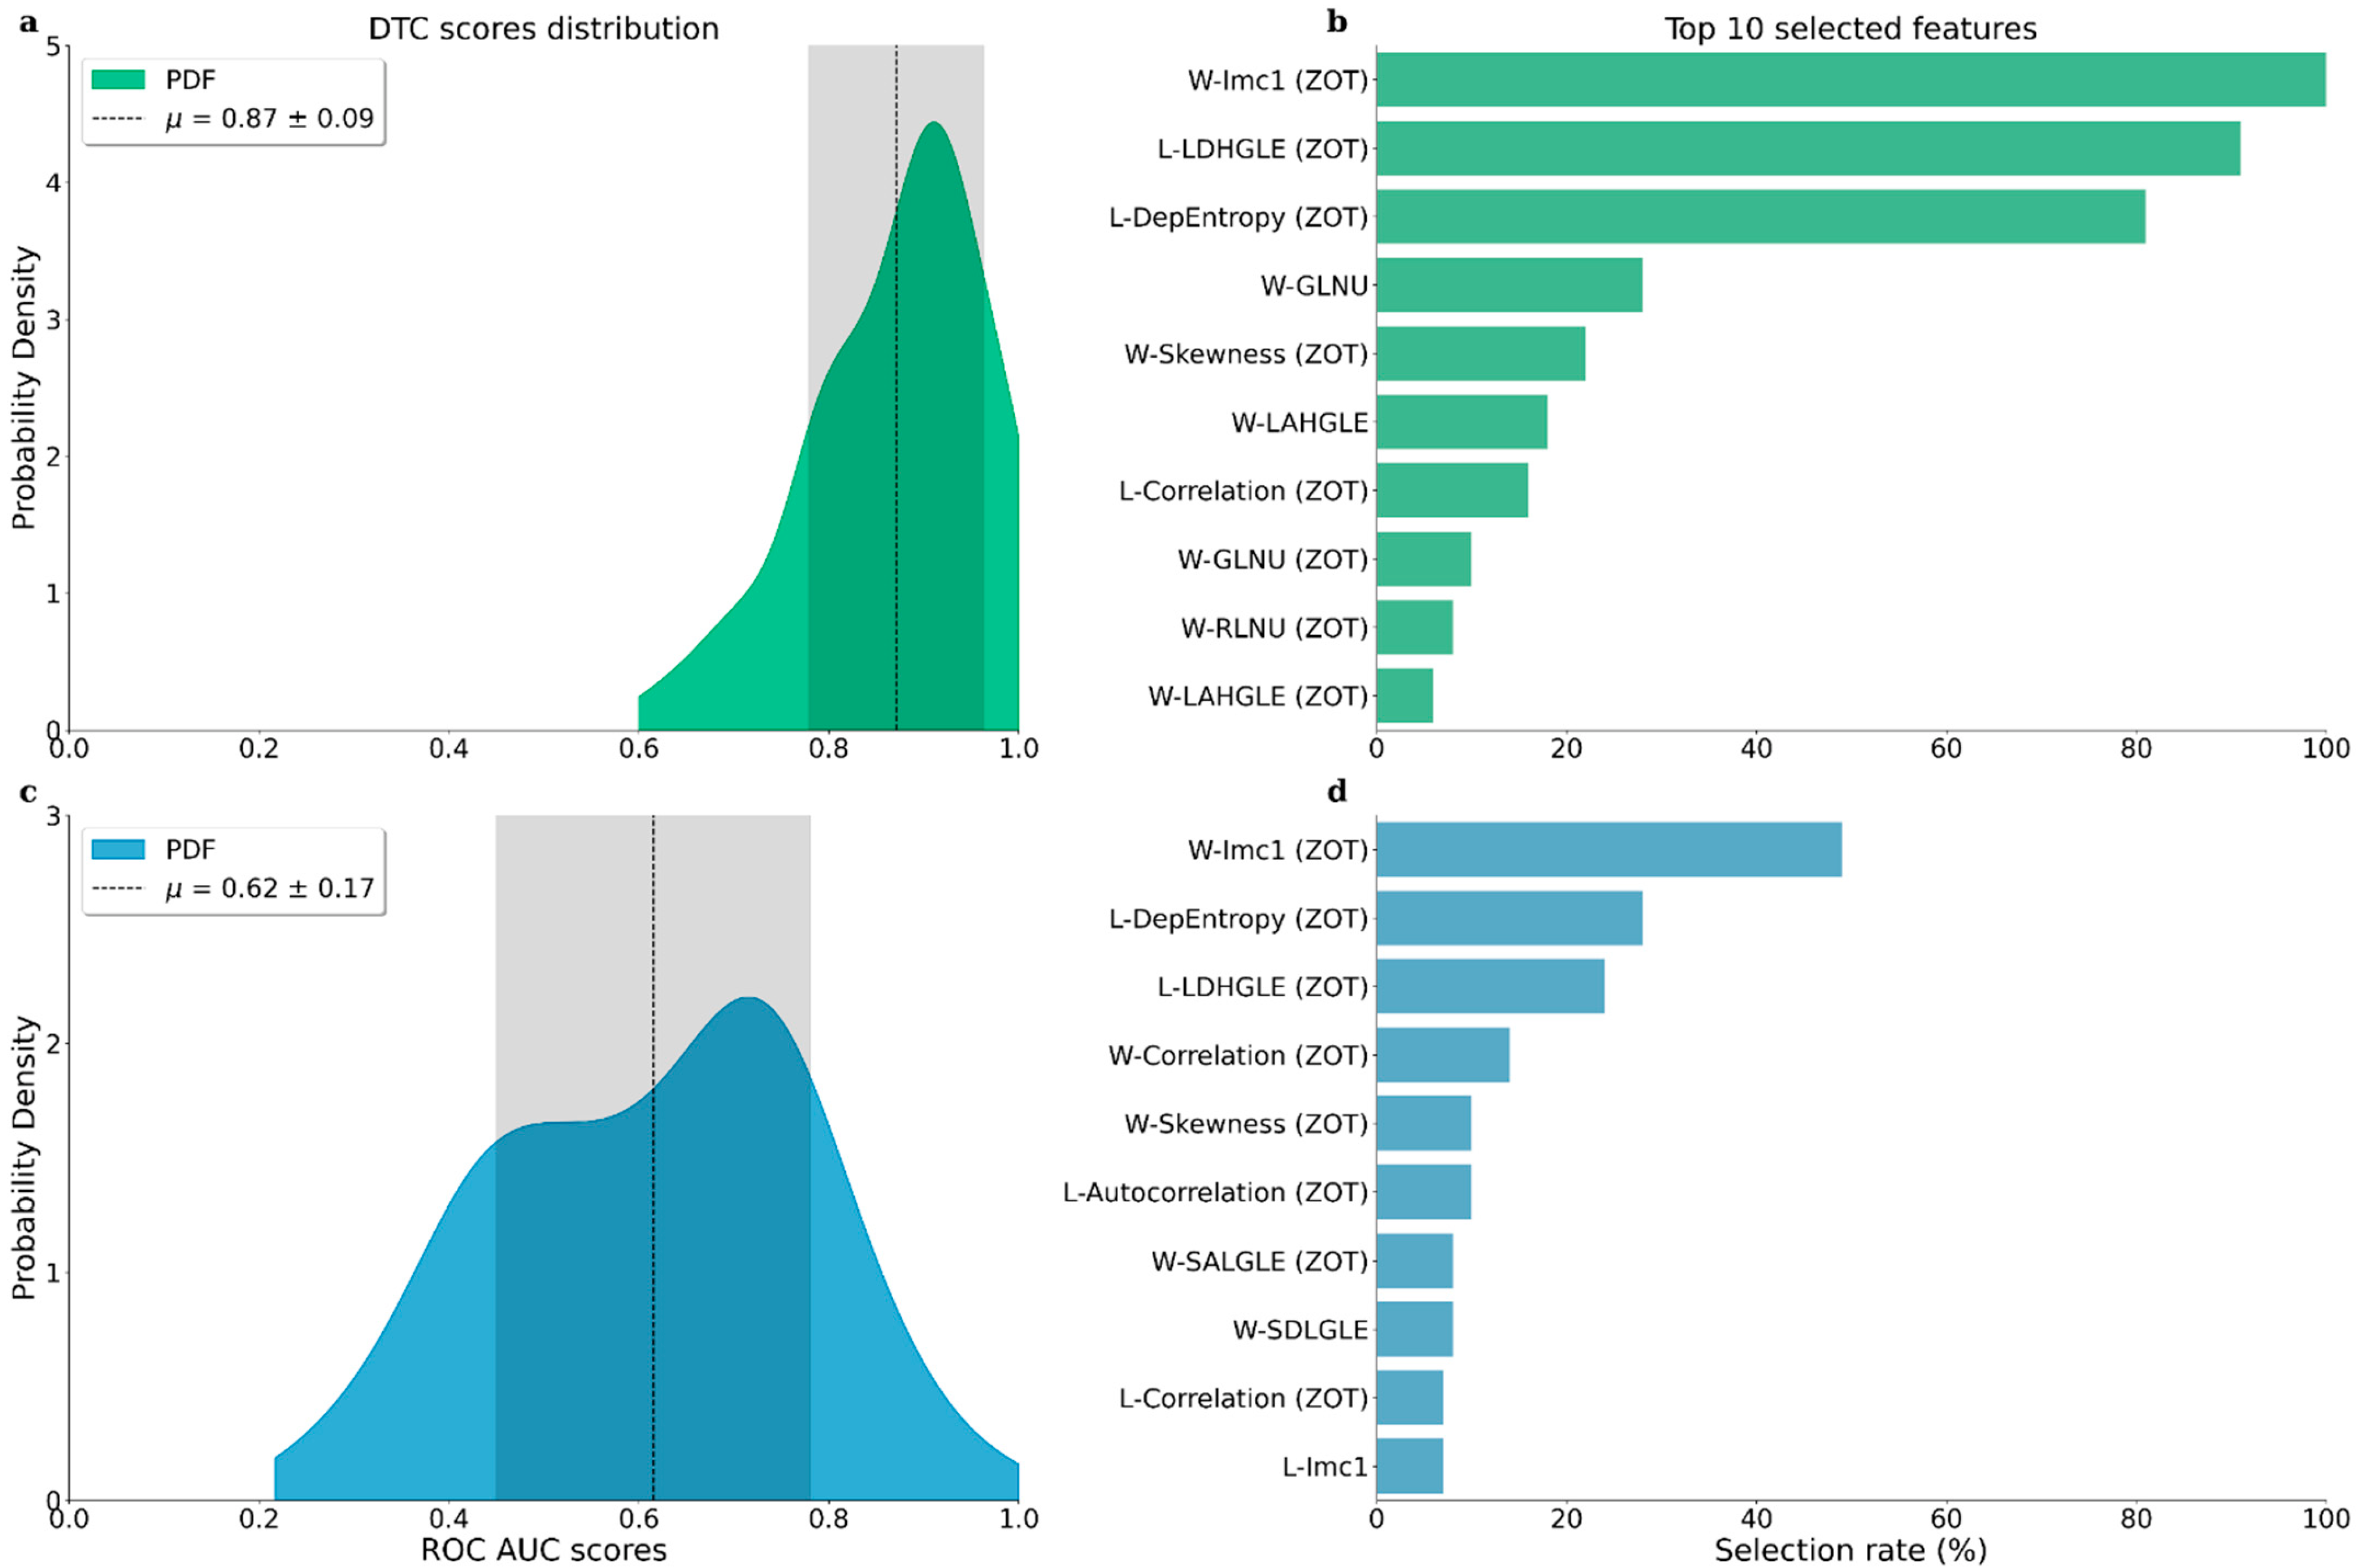

2.4. Classification Model

3. Results